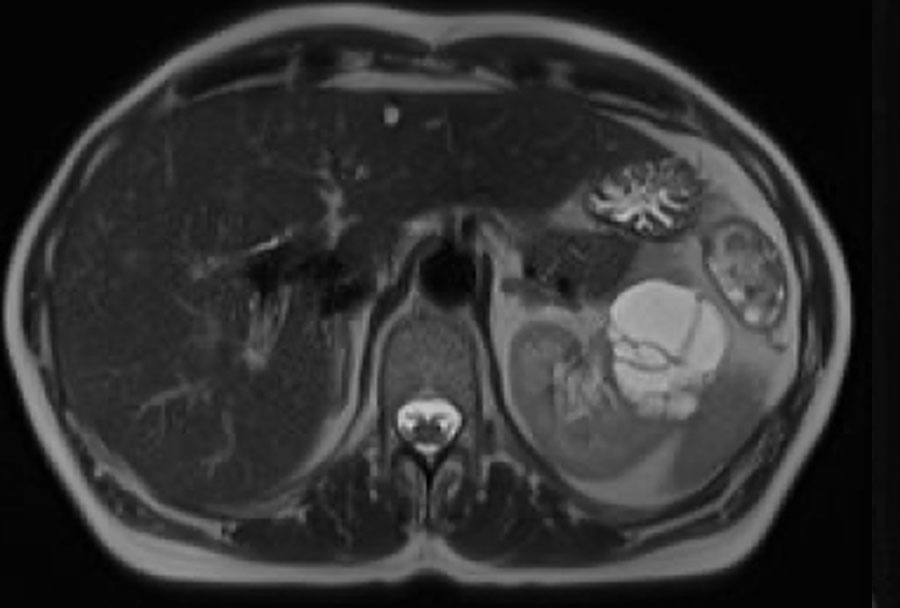

Có một khối dạng nang ở thận phải với nhiều (> 4) vách ngăn mỏng, nhẵn, có ngấm thuốc.

Tổn thương được phân loại là Bosniak IIF.